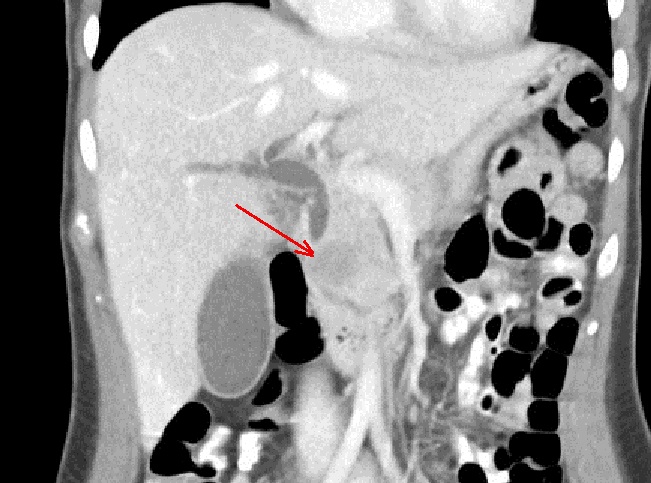

Aspect TDM tres volumineuse

hypodensite heterogen ,bien circoncrite et encapsule

situe du corp pancreas . Sa contenue est non

homogene , rehaussement legere apres injection de

contrast intraveineuse . Image radiologique TDM plus

C+ en coupe axiale phase veineuse |

|

Meme cas en coupe coronale .

La tumeur agresse tres volumineuse a longitudinal du

corp pancreas . |

Une tumeur acinaire tres volumineuse de la tete du

pancreas avec aspect lesionnel d'une masse hypodensite non homogene

, encapsule a bord tres nette ( fleche rouge ) .

Zone de nesrose kystique se retrouve dans 1/3 de la

tumeur . Image radiologique TDM en coupe axilaire |